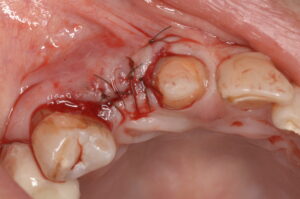

抜歯後です。だいぶ凹んでいます。